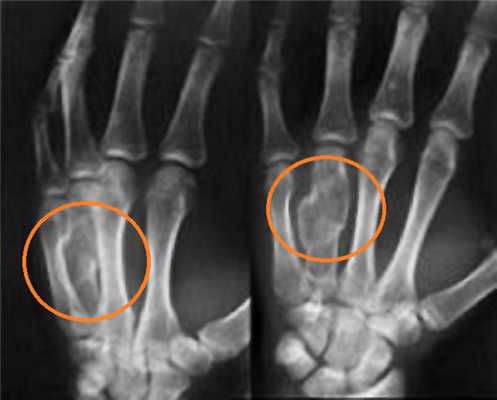

В зависимости от уровня повреждения вывихи пальцев рук подразделяются на вывихи основной, средней и ногтевой фаланги. При вывихе основной фаланги ее суставная поверхность смещается относительно головки соответствующей пястной кости. При вывихе средней и ногтевой фаланги суставная поверхность дистально расположенной фаланги смещается по отношению к проксимальной. В зависимости от направления смещения выделяют тыльные, ладонные и боковые вывихи. Чаще всего наблюдается смещение кости в тыльную сторону. При вывихах пальцев стопы возможно повреждение в области межфалангового и плюснефалангового сустава. Дистальный сегмент может смещаться в подошвенную, тыльную или боковую сторону.

Вывихи проксимальных фаланг II-V пальцев

Обычно возникают тыльные вывихи. Повреждение сопровождается резкой болью, деформацией, отеком мягких тканей. Движения в пястнофаланговом суставе невозможны, определяется пружинящее сопротивление. На ладони пальпируется головка соответствующей пястной кости, на тыле - суставная поверхность основной фаланги. Диагноз подтверждается при помощи рентгенографии пальцев кисти. Лечение амбулаторное - закрытое вправление под местной анестезией с последующей иммобилизацией в течение 3 недель. В этом периоде назначается УВЧ и функциональная терапия. Больничный лист закрывают через 4-5 недель.